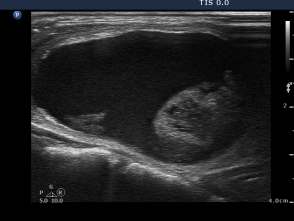

First session of sclerotherapy (second row of images):

Palpation: unchanged.

Ultrasonography remained unchanged.

We could aspirate 2 ml thick, brown cystic fluid and injected 3 mL ethanol.